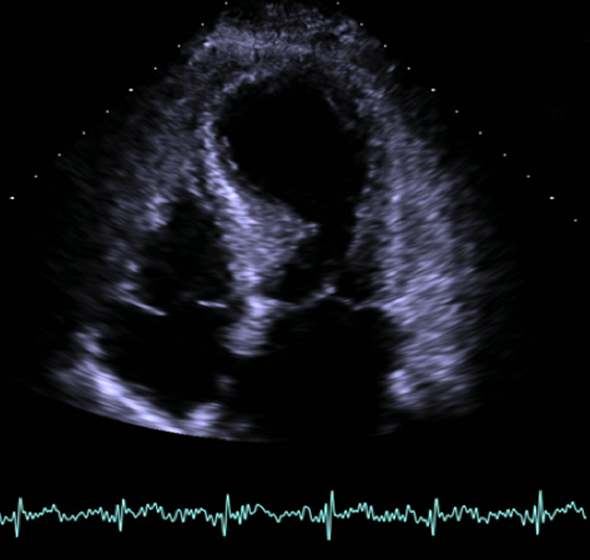

El resultado de la coronariografía fue: arterias coronarias sin lesiones. Depresión moderada-grave de la FEVI por extensa discinesia de los segmentos medio-apicales. Se completa estudio con ecocardiografía y RM cardiaca.

- E. Miocardiopatía de estrés con realce tardío no típico.